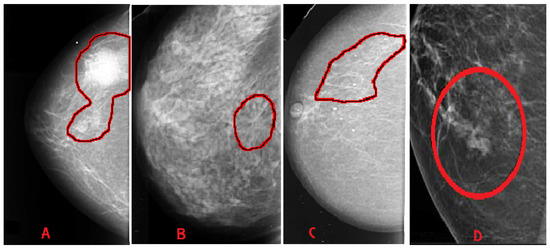

- Mass: A mass is a 3D lesion that can be seen in various projections. Morphological features, such as shape, margin and density, are used for mass characterisation. The shape can be round, oval or irregular. The margin can be not well defined, microlobulated, speculated, indistinct or circumscribed. Figure 4 shows the graphical representation of these morphological features (shape and margin) of a mass along with their subcategories. When superimposed breast tissues hide margins, that is called obscured or partially obscured. Microlobulated infers a suspicious finding. Spiculated margin with radiating lines is also a suspicious finding. Indistinct, also termed as ill-defined, is a suspicious finding too. Circumscribed is a well-defined mass that is a benign finding. Density can be high, low or fat-containing. The density of a mass is related to the expected attenuation of an equal volume of a fibroglandular tissue [6,20]. High density is associated with malignancy.

- Architectural distortion: This abnormality is found when normal architecture is distorted without certain mass visibility. Architectural distortion may include straight thin lines, speculated radiating lines, or focal retraction [6,20]. This abnormality can be seen as an additional feature. If there is a mass with distortion, it is likely to be malignant.

- Calcification: Calcifications are tiny spots of calcium that develop in the breast tissues. Arrangement of calcifications can be diffuse, regional, cluster, linear or segmental [6,20]. There are two types; macrocalcification and microcalcification. Macrocalcifications are large dots of white colour and often spread randomly within the breast area. Microcalcifications are small deposits of calcium, usually non-cancerous, but if visualised as particular patterns and clustered, they may reveal an early sign of malignancy.